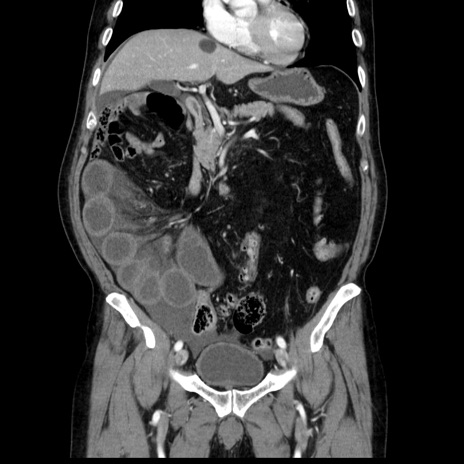

症例30(冠状断像)

【症例】80歳代男性

【主訴】臍周囲痛

【現病歴】約6時間前から臍下部痛が出現。次第に腹部膨隆・背部痛も生じてきたため来院。背部痛の場所は変化しない。

【既往歴】腎盂腎炎

【身体所見】意識清明、BT 36.3℃、BP  131/87mmHg、P 87bpm、SpO2 100%(RA)、臍周囲自発痛・圧痛あり、反跳痛なし、自発痛部位に一致して板状硬あり、腹部膨隆、腸雑音減弱、CVA tenderness両側陰性。

【データ】WBC 19600、CRP 0.33